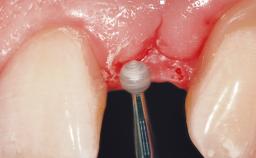

Surgical treatment of a 67-year-old male patient exhibiting an extended edentulous space in the anterior maxilla after the removal of three hopeless incisor teeth.

The video demonstrates implant placement using a surgical stent according to the principle of prosthodontically driven implant placement. The deficient ridge is augmented with locally harvested autologous bone chips, a superficial layer of xenogenic DBBM particles and a resorbable collagen membrane. The surgery is completed with a precise, tension-free primary wound closure.